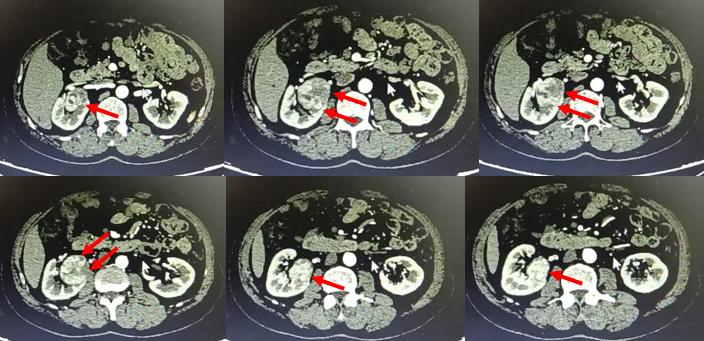

在手术前,朱绍兴教授团队利用3D成像技术,将CT影像二维数据在计算机上进行三维重建,将肾脏血管、集合系统与肿瘤的空间关系做了多角度的直观显示,进而制定了详实的手术计划和预案。

▲图1:术前肾脏CT影像及三维重建图,可见肿瘤嵌入肾门中央,被肾脏大血管所包绕(红色箭头所指处为肾肿瘤,三维重建图中绿色部分为肾肿瘤、红色部分肾动脉、蓝色部分为肾静脉、青色部分为肾脏、黄色为输尿管肾盂)

“以前就算开刀进入肾脏内部,也无法看得这么清楚。现在通过三维重建技术,医生在术前就能准确地评估病变周围情况,依此模拟手术场景、规划手术路径,为最大限度地在切除肿瘤的同时,保留肾内大血管和其他重要结构且最大程度地保留肾单位奠定基础。” 02 精确定位肿瘤:腔内超声“透视眼”助力精准定位肿瘤